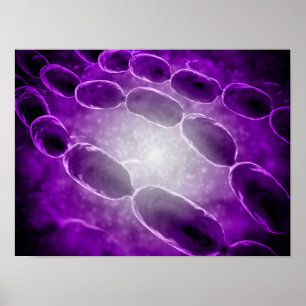

Human Heart Lungs Anatomy 1902 Print

Prijs€ 23,90